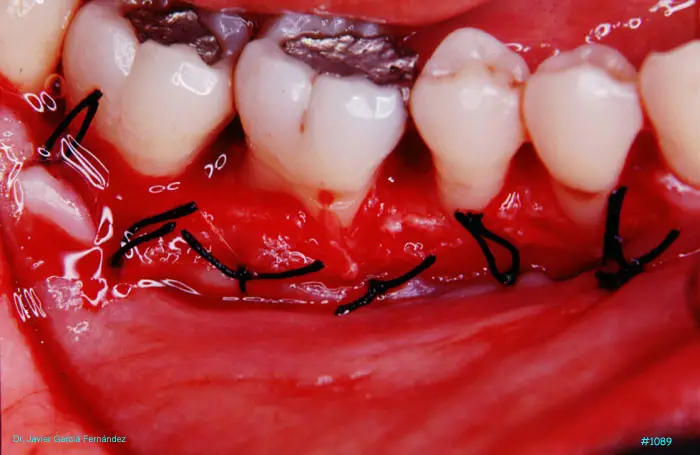

Atlas of Surgical Techniques in Periodontics. Chapter III. Atlas de Técnicas Quirúrgicas en Periodoncia